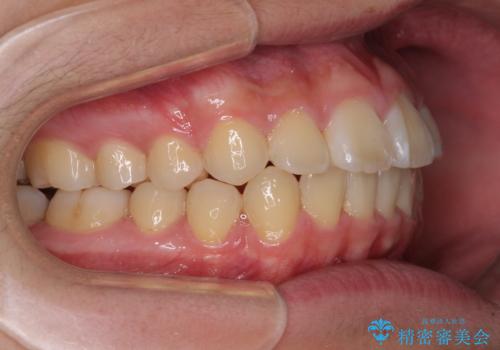

前歯のデコボコを短期間で治療 目立たないワイヤー矯正

- 矯正装置

- 審美装置

- 上下前歯のデコボコを改善したいとのことで来院された患者様です。

自己管理を減らしたいとのことで、ワイヤー装置による矯正治療を行うこととしました。

中学生と言うこともあり、1年強の短期間で終了しました。

歯磨きがしっかりとできないと虫歯になるリスクがありましたが、治療期間中は清潔な状態を保っていただけました。